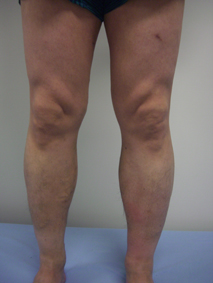

【東近江】 医療法人敬愛会東近江敬愛病院(東近江市八日市東本町)は、下肢静脈瘤(かしじょうみゃくりゅう)の血管内焼灼(しょうしゃく)術で用いる最新鋭の医療機器を導入し、今年2月から治療を始めている。

この血管内焼灼術は、静脈瘤を起こす血管内にカテーテルを挿入し、熱を発生させ、患部の血管をふさぐ治療法。静脈瘤が治癒すれば、下肢の疲労感や重量感、鈍痛、こむら返り、かゆみ、むくみといった自覚症状も改善できる。